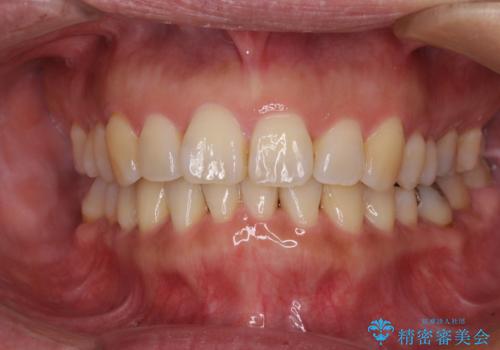

前歯の変色している歯は、神経組織が壊死していたため、矯正治療前に根管治療を実施し、矯正治療後にオールセラミッククラウンにて補綴治療を行うこととしました。

順調に歯が動き、補綴治療も含め2年弱で治療を終えることができました。